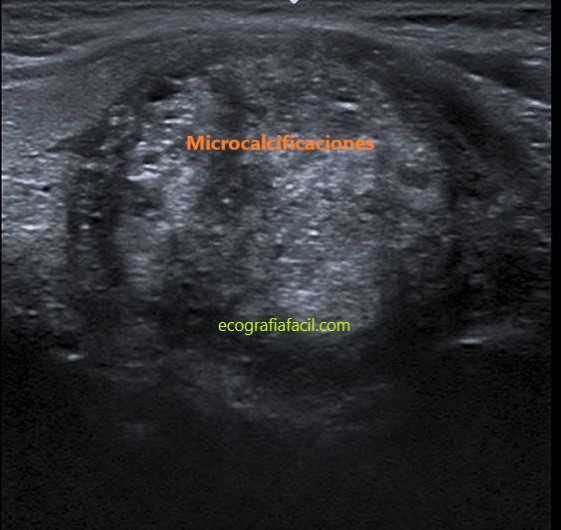

FOCOS ECOGÉNICOS PUNTIFORMES:

Los focos ecogénicos puntiformes son más pequeños que las macrocalcificaciones y no tienen sombra. En los componentes sólidos de los nódulos pueden corresponder a calcificaciones en cánceres papilares y por tanto se consideran de alta sospecha de malignidad particularmente asociados en combinación con otras características sospechosas.